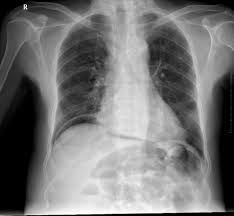

Pneumoperitoneum common signs and symptoms are abdominal pain, vomiting, abdominal distension, constipation, fever, diarrhea, tachycardia (pulse >110/min), hypotension (systolic blood pressure <100 mmHg), urine output (<30 mL/hour), and tachypnea (respiratory rate >20/min) 7